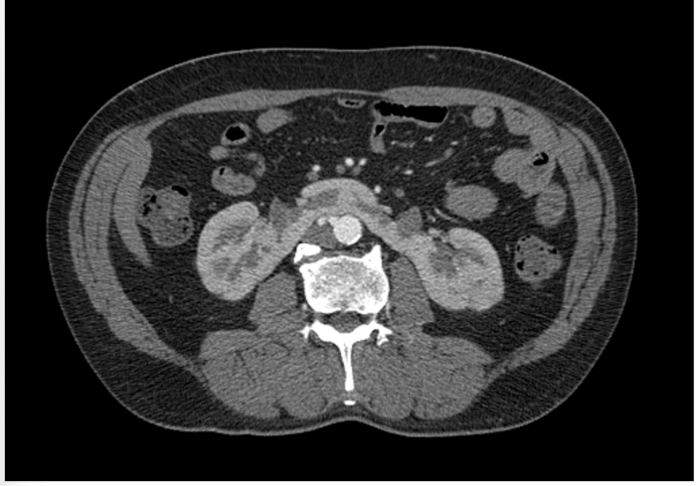

Analise a imagem de tomografia computadorizada abaixo e avalie as assertivas que seguem.

Figura 4 –Tomografia computadorizada do rim.

Fonte: CPCON.

I- A imagem corresponde à anomalia de fusão denominada rim em ferradura, em que há a fusão dos polos inferiores dos rins na linha média.

II- O achado acima é compatível com rim discoide. Nesses casos, a drenagem ureteral sempre é feita por ureter único.

III- Pacientes que apresentam esta anormalidade de fusão têm aumento da incidência de neoplasias, como carcinoma de células transicionais.

IV- Trata-se de uma ectopia renal cruzada com fusão.

V- O local onde há a fusão pode apresentar tecido fibroso ou parênquima renal.

É CORRETO o que se afirma apenas em: